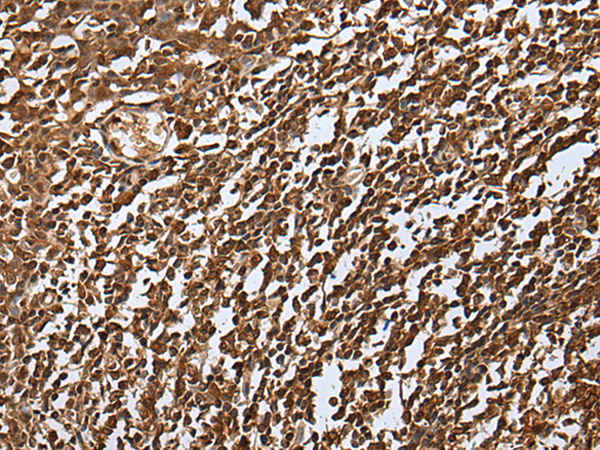

分类: 科研抗体货号: P09349别名: G5; BAT4; D6S54E; ANKRD59; GPATCH10应用: IHC反应种属: Human, Mouse